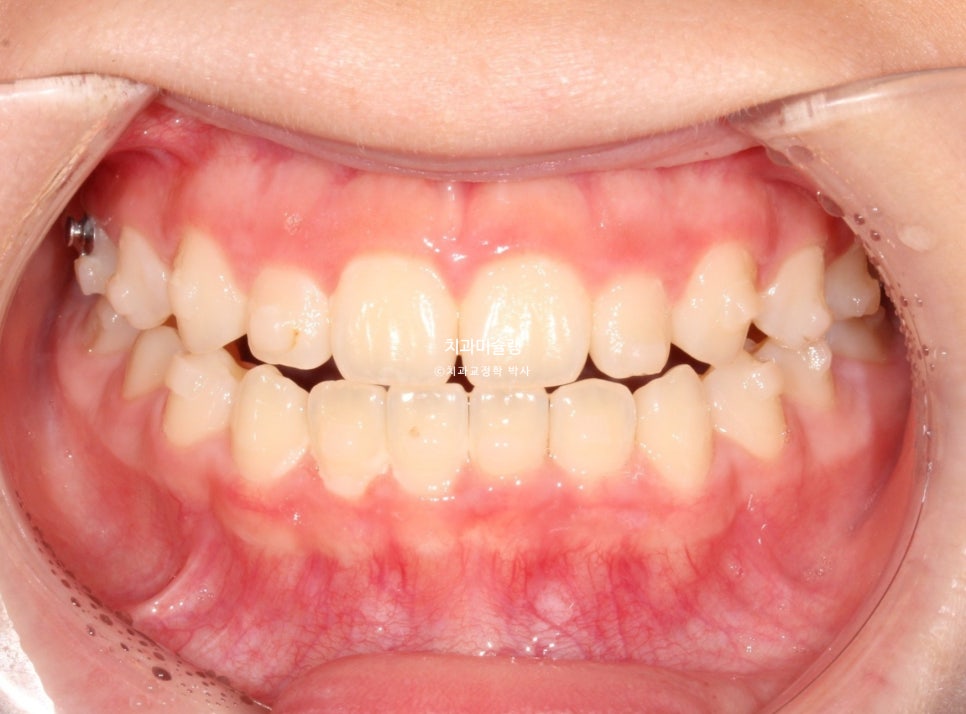

2026년 2월 – 치료 완료

2026년 2월, 정상교합이 달성되어 치료를 마무리 합니다.

중심선은 잘 맞으며 절단교합으로 인항 개방교합은 해소되었습니다.

어금니 교합관계는 1급을 달성.

3급 교합관계를 1급으로 만들기 위해 치료기간 내내 3급 고무줄을 사용했습니다.

결과가 성인교정치료 결과에 준한만큼 유지장치도 성인과 동일하게 들어갑니다.